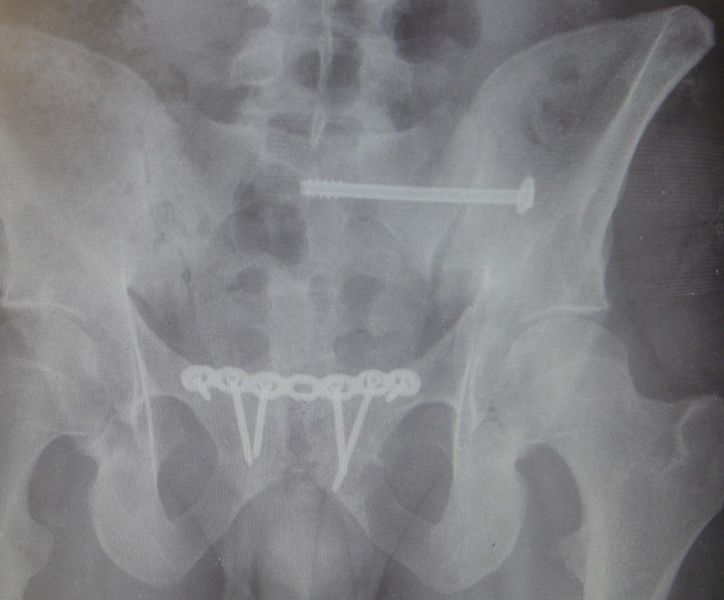

3. Pelvic fracture called also open book fracture in a 27-year-old male.

Treatment: Open reduction internal fixation of pubic symphysis and percutaneous fixation of the left sacroiliac joint

I. Before surgery II. Post-surgery, anteroposterior x-ray of pelvis showing one plate and six screws in pubic symphysis and one large screw in the left sacroiliac joint